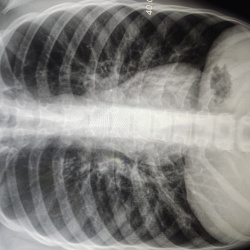

Здравствуйте! Молодой человек пришёл на комиссию, есть ли справа кальцинаты? Также интересует тень на фоне 2 межреберья слева на фоне сосудов - тоже сосуд? Второй снимок выполнен в задней проекции....